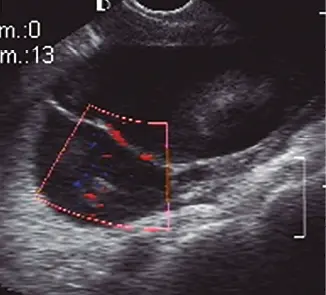

Fig: 9–b

Fig: 9–b, pieza quirúrgica la cual corresponde un Ca renal mixto: sólido–quístico.